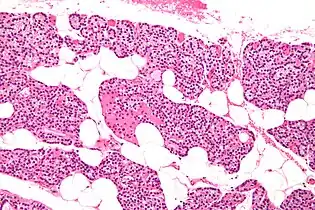

The parathyroid glands are named for their proximity to the thyroid—and serve a completely different role than the thyroid gland. The parathyroid glands are quite easily recognizable from the thyroid as they have densely packed cells, in contrast with the follicular structure of the thyroid.[6] Two unique types of cells are present in the parathyroid gland:

- Chief cells, which synthesize and release parathyroid hormone. These cells are small, and appear dark when loaded with parathyroid hormone, and clear when the hormone has been secreted, or in their resting state.[7]

- Oxyphil cells, which are lighter in appearance and increase in number with age,[7] have an unknown function.[8]

Intermediate magnification micrograph. H&E stain. The white round structures are fat cells. Adipose tissue comprises 25–40% of normal parathyroid gland tissue.[7]